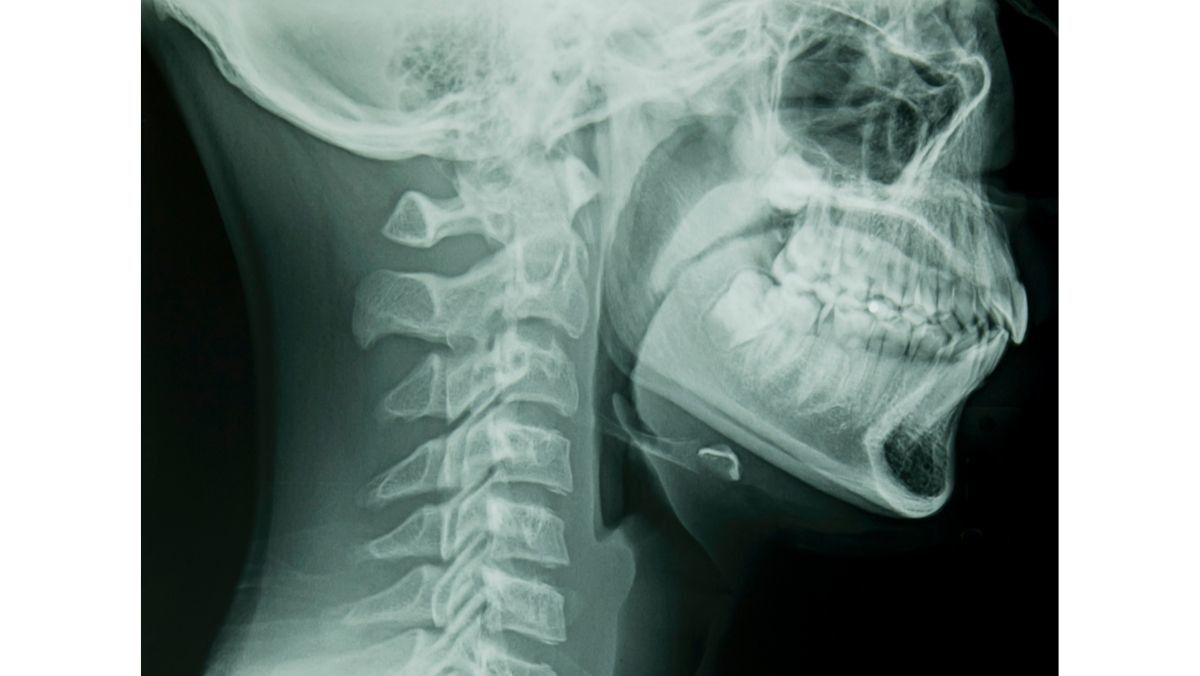

Anatomi dan Struktur Faring

Faring memiliki tiga bagian penting, yaitu nasofaring, orofaring, dan laringofaring. Berikut penjelasannya:

- Nasofaring: Bagian atas tenggorokan ini terhubung ke rongga hidung dan sebagai tempat masuknya udara.

- Orofaring: Bagian tengah tenggorokan ini terhubung ke rongga mulut dan menjadi tempat udara, makanan, atau cairan masuk ke dalam tubuh.

- Laringofaring atau hipofaring: Bagian ini letaknya di bawah tenggorokan dekat laring (kotak suara). Laringofaring berfungsi mengatur masuknya udara ke paru-paru serta mengatur makanan dan cairan masuk ke kerongkongan.